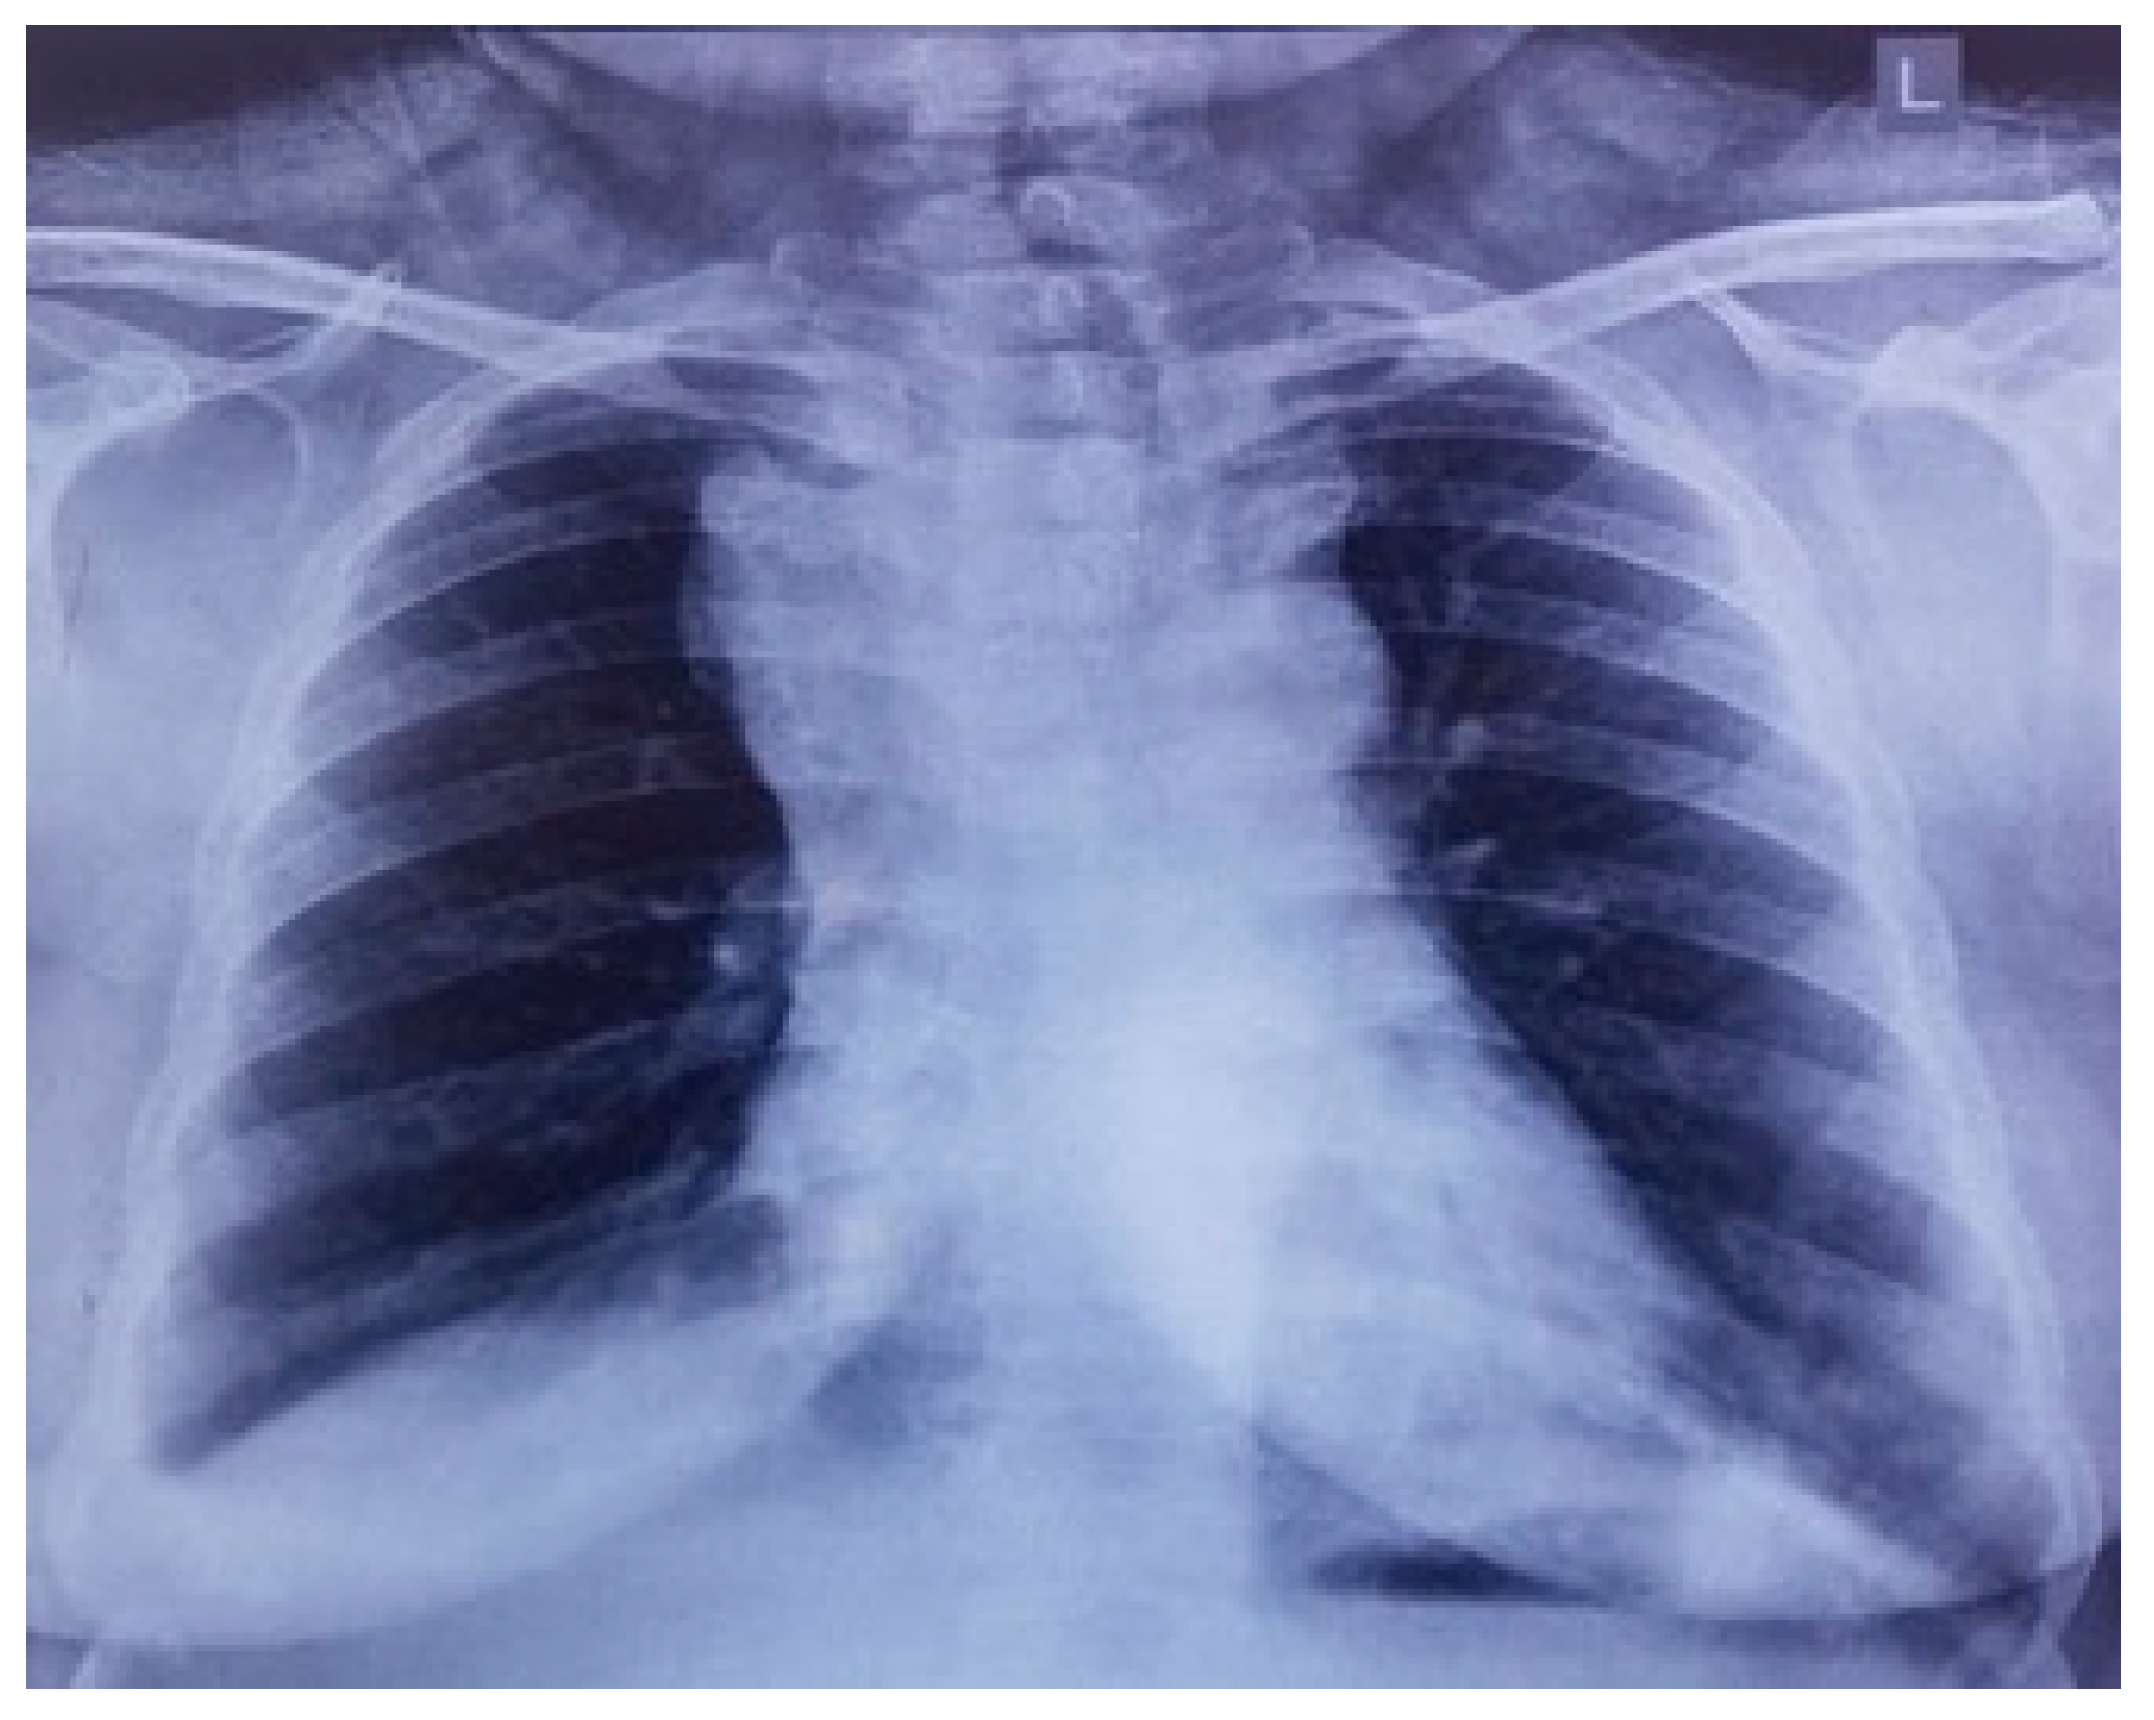

On preliminary examination, the patient was conscious with tachypnoea and tachycardia. She had puffiness with the flushing of the face, periorbital region, and neck. Oedema of both upper limbs was also noted. Jugular venous pressure was elevated, and the rest of the systemic examination was unremarkable. Preliminary blood reports were within normal limits, and a chest X-ray showed a large mass with respect to the mediastinal compartment obscuring the bilateral hila and arch of the aorta (Figure 1).

Figure 1. Chest X-ray showing widened superior mediastinum.